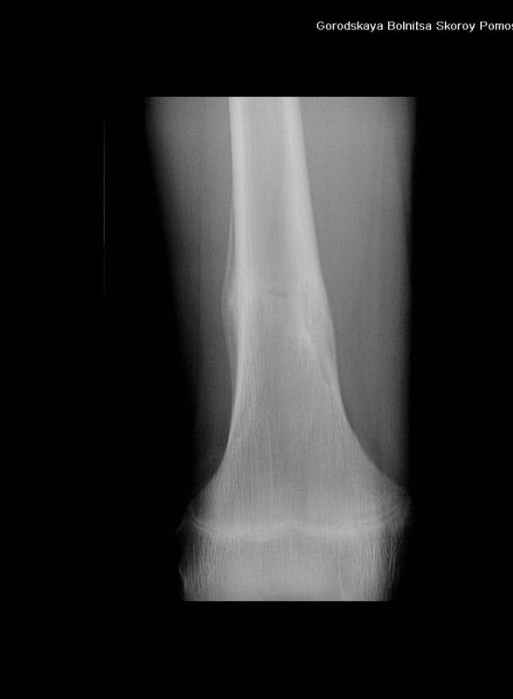

Здравствуйте, уважаемые коллеги!Представляю вашему вниманию интересный случай и пока что непонятный для меня в диагностическом плане. На днях в наше отделение (детской ортопедии и травматологии) поступил 13-летний мальчик по направлению из поликлиники с диагнозом: остеома нижней трети правого бедра.

Анамнез практически никакой: в следствие травмы (растяжение связок коленного сустава) от 07.11.2004 выполнены Rg-граммы в травмпункте и обнаружено опухолевидное образование. Первичные Rg-граммы я не публикую, так как они заметно худшего качества, да и динамики за прошедшие три недели не отражают. Болевой синдром купирован в течение трёх дней. В настоящий момент мальчика ничего не беспокоит. Ходьба не нарушена, опухоль пальпируется с трудом по задней поверхности в н\3 правого бедра, пальпация безболезненна, объем движений в суставах правой нижней конечности полный и симметричный. Кожа над опухолью не изменена.В нашей клинике проведено дополнительное обследование: общие анализы крови и мочи, биохимия крови без особенностей. Выполнены Rg-граммы на цифровом Siemens обычные и продольные томограммы срезами 3-5 мм, а также компьютерная томография поперечными срезами по 5 мм. Прошу обратить внимание, что на приведённых томограммах видны две полости 10х15 мм и 15х60 мм. Также имеются два опухолевидных образований наслаивающихся друг на друга: уплощённое и вытянутое 10х100 мм и элипсовидной формы 15х30 мм. Это хорошо заметно на фото a_1.jpg c_1.jpg и d_1.jpg. Плотность внутри полостей 125% от плотности костномозгового канала, плотность наружного опухолевидного образования 55% от плотности кортикального слоя. Также отмечается линия перелома по центру наружного опухолевидного образования.Исходя из полученных данных мнения в плане диагноза несколько разделились от 1)сочетания кортикальной фиброзной дисплазии и латентно протекавшего маршевого перелома н\3 правого бедра до 2)остеосаркомы. В отношении первого варианта не сходится отсутствие клиники при переломе такой крупной кости как бедро, второй вариант вообще оставлю без комментария, ибо некомпетентен. Хотелось бы услышать мнения коллег, с удовольствием ознакомлюсь с любыми предположениями и замечаниями.С уважением, Александр Е. КлоковОтделение детской ортопедии и травматологииБСМП г. Мурманска.